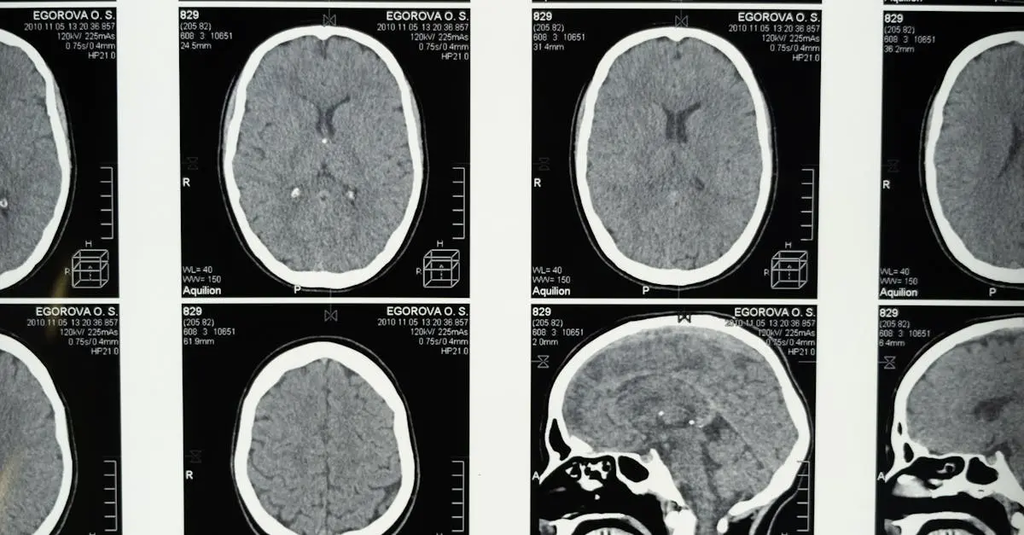

Researchers use brain imaging (e.g., MRI, fMRI) to measure brain structure and function, genetic analyses (e.g., GWAS) to identify gene variants, twin studies for heritability estimates, and polygenic scores to summarize genetic influence.